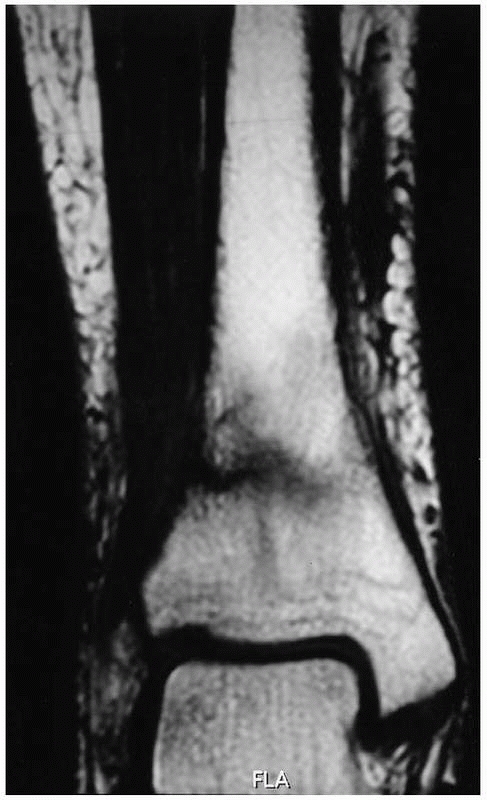

the cortex and medullary space57,66 (Fig. 19-2).

FIGURE 19-2

Coronal T1-weighted magnetic resonance image of a Grade 4 distal tibia stress fracture with visible fracture line and surrounding marrow edema. |